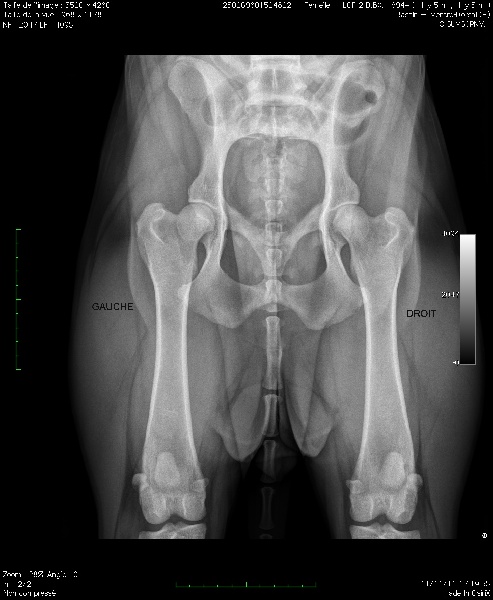

COUDES O/O